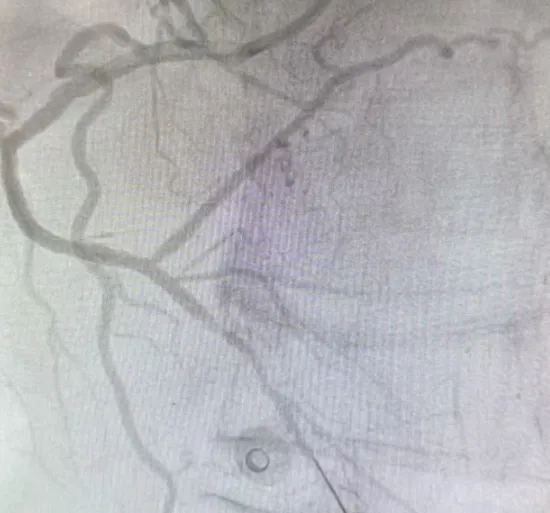

心内科检查后发现,患者心脏的一根主要血管——右冠状动脉,从近端到远端弥漫性狭窄,严重处达99%,远段已形成慢性完全闭塞;左冠回旋支也存在多处严重狭窄。

术中,夏文龙、陈龙医生团队交替使用多种工作导丝与CTO专用导丝,利用血管解剖特点,逐步探查闭塞血管的通道,在不懈努力下,血流恢复通畅,支架顺利植入。